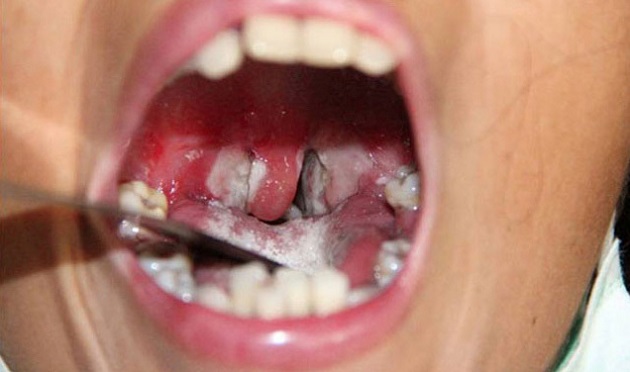

- Bệnh bạch hầu họng và amidan: Bệnh nhân mệt mỏi, đau cổ họng, chán ăn, sốt nhẹ. Sau 2-3 ngày, sẽ xuất hiện một đám hoại tử tạo thành lớp giả mạc màu trắng xanh, dai và dính chắc vào amiđan, hoặc có thể lan rộng bao phủ cả vùng hầu họng. Thường thể bệnh này các độc tố ngấm vào máu nhiều và có thể gây tình trạng nhiễm độc toàn thân. Một số bệnh nhân có thể sưng nề vùng dưới hàm và sưng các hạch vùng cổ làm cổ bạnh ra như cổ bò. Những trường hợp nhiễm độc nặng bệnh nhân sẽ phờ phạc, xanh tái, mạch nhanh, đờ đẫn, hôn mê. Các bệnh nhân này nếu không được điều trị tích cực có thể tử vong trong vòng 6-10 ngày.

- Bạch hầu thanh quản: Đây là thể bệnh tiến triển nhanh và rất nguy hiểm. Bệnh nhân thường biểu hiện bằng dấu hiệu sốt, khàn giọng, ho ông ổng. Khi khám, bác sĩ có thể thấy các mảng giả mạc tại ngay thanh quản hoặc từ hầu họng lan xuống. Nếu không được xử trí kịp thời, các giả mạc này có thể gây tắc đường thở làm bệnh nhân tử vong nhanh chóng.